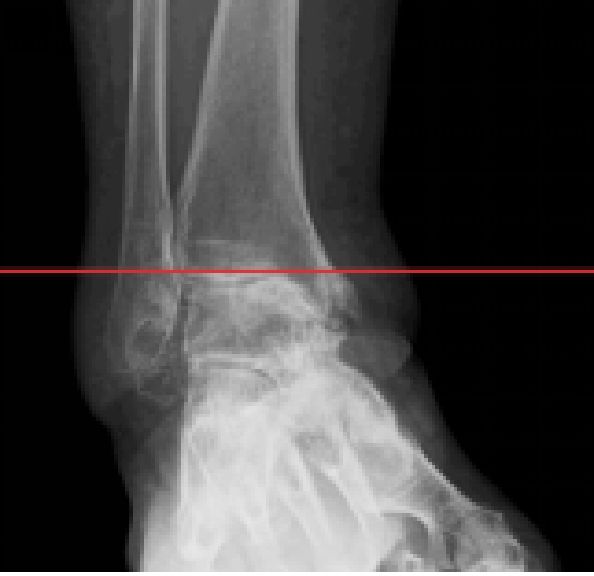

足首の痛みと変形 変形性足関節症、距骨壊死、距骨骨軟骨障害

新鮮骨折と遺残障害 足関節の果部骨折・脱臼骨折、踵骨関節内骨折、距骨骨折

新鮮靭帯損傷と遺残障害 足関節外側靭帯損傷、リスフラン靭帯損傷、足関節ねんざ後の遺残疼痛(足根洞症候群など)、距骨下関節不安定症

の外科的治療:症例

保存療法では治療が見込めない患者様に対しては、人工足関節置換術、矯正骨切り術、遠位脛骨斜め骨切り術、関節固定術、血管柄付き腓骨移植、再建術などの外科的治療を提案をしております。

外科的治療:症例一覧